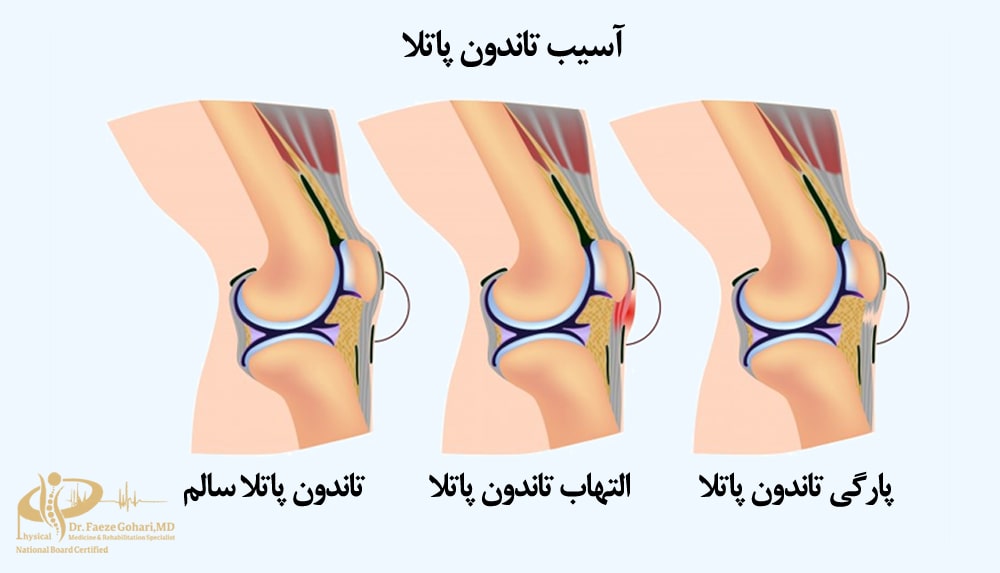

آسیبهای تاندون

در حالی که PRP برای همة آسیبهای تاندونی زانو یا مواردی مانند پارگی کامل تاندون مناسب نیست، در پارگیهای جزئی و التهاب تاندون و همچنین در درمان تاندونیت پاتلار (معروف به زانوی برشکاران) نتایج امیدوارکنندهای داشته است، بهویژه در صورت انجام تزریقهای متعدد و پیگیری بلندمدت.

بااینحال، برتری آن نسبت به سایر درمانهای غیرجراحی مانند شاکویوتراپی (ESWT) یا تمرینات اکسنتریک هنوز به طور کامل اثبات نشده است. اثربخشی این روش به عواملی مانند نوع فرمولاسیون PRP، تعداد تزریقها و شرایط بالینی بیمار بستگی دارد (منبع). تصمیمگیری در این زمینه بهتر است با مشاورة پزشک متخصص انجام شود.